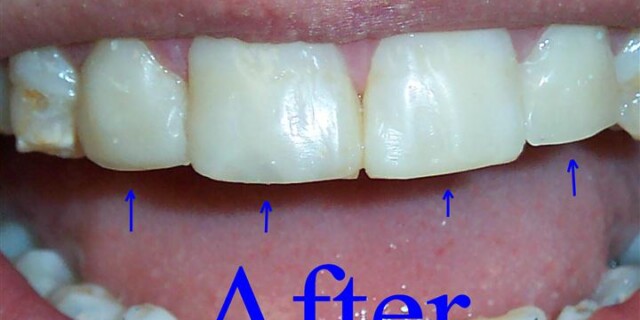

Dental Bonding